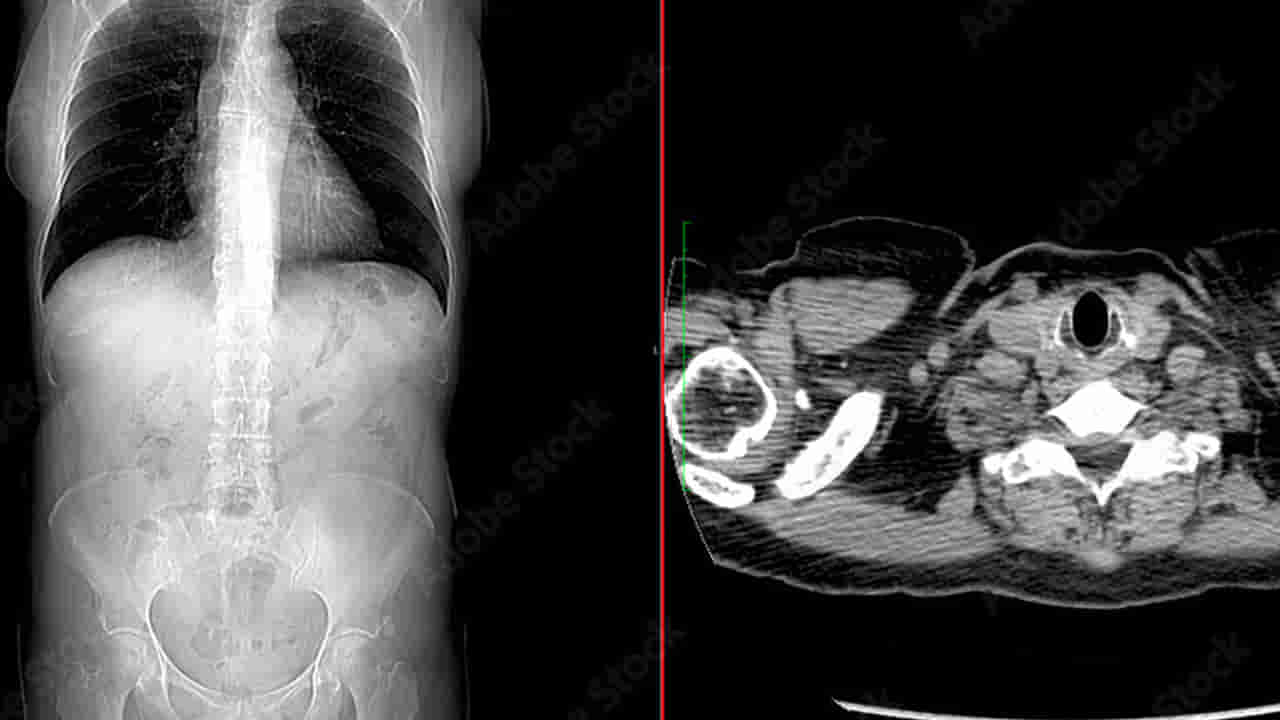

డాక్టర్ రాజీవ్ సింగ్, డాక్టర్ విషాల్ కేవలాని, డాక్టర్ యోగేంద్ర, డాక్టర్ రాజ్ మౌర్యల బృందం కలిసి రెండు గంటలపాటు శస్త్రచికిత్స జరిపారు. కడుపు ఓపెన్ చేయగా 1.5 అడుగుల పొడవు, 10 సెం.మీ వెడల్పు, సుమారు 500 గ్రాముల బరువు ఉన్న హెయిర్ బాల్ కనిపించింది. దాన్ని జాగ్రత్తగా తీసి, పేగులన్నీ శుభ్రం చేసి, దెబ్బతిన్న భాగాలకు చికిత్స చేశారు.

ఈ యువతికి ట్రికోఫేజియ అనే అరుదైన మానసిక రుగ్మత ఉంది. ఈ వ్యాధితో బాధపడే వాళ్లు జుట్టు, మట్టి, గాజు వంటివి తినే అలవాటు కలిగిఉంటారు. చిన్నప్పటి నుంచి తన జుట్టు, కొన్నిసార్లు ఇతరుల జుట్టూ ఆమె తినేదని.. ఆ జుట్టు కడుపులో ఓ బాల్ మాదిరిగా పేరుకుపోయిందని వైద్యులు తెలిపారు. ఈ హెయిర్ బాల్ సమయానికి తీసేయకపోతే.. పేగుల్లో అడ్డంకులు ఏర్పడి.. లోపల విష పదార్థాలు పేరకుపోయి..జీర్ణక్రియ వైఫల్యం, చివరికి మరణం కూడా సంభవించేదట.